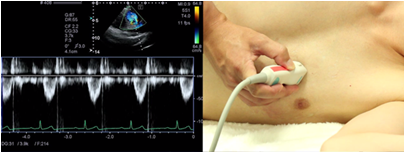

Left ventricular inflow pattern

The left ventricular inflow pattern is recorded in the apical longitudinal view or the apical 4 chamber view. Try your best to set a view in which the Doppler beam is in parallel with the left ventricular inflow. The position of the sample volume is set at the distal tip of the mitral valve. The left ventricular inflow pattern is used for measurement of early diastolic waves (E-waves), atrial systole wave (A-wave), and deceleration time of E-wave (DcT). You must be careful because the velocity of E- and A-waves and the E/A ratio change when the position of the sample volume is changed.